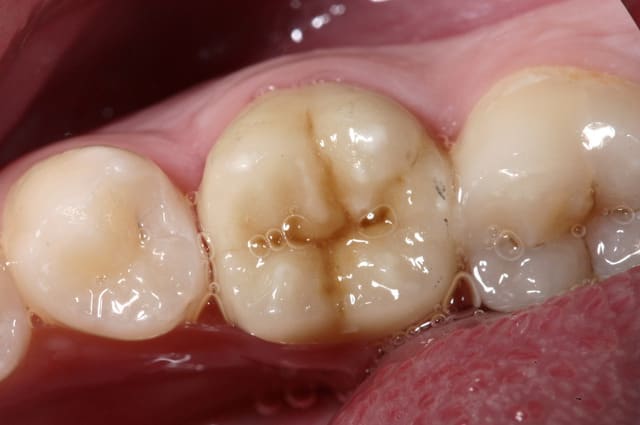

pour enfoncer le clou sur les tenons et autre inlay core

ne pas perdre de vue qu'un tenon = Rétention ... c'est tout !

Si on a de la rétention autrement, pas besoin de tenon...

Un tenon fragilise la racine et réduit l'étanchéité du traitement endo...

un cas comme on peut en faire souvent, d'endo couronne collée, exploitant le volume de la chambre pulpaire...

Et j'ajouterais que sur les photos que tu nous montres, tu as as réalisé un trottoir périphérique, pour réaliser qqchose qui ne correspond pas à la définition traditionnelle d'une endocouronne (qui est en réalité un onlay, avec prise de rétention interne).

Il est possible que l'ajout de férule par ce moyen permette au dispositif de fonctionner, mais dans ce cas, quel intérêt par rapport à une reconstitution composite avant couronne traditionnelle ?

C'est pas mal comme restauration, toutefois, tu as eu un peu de chance car l'endocouronne ne se prépare pas comme cela.

Tu a fais un mix entre la coiffe périphérique et l'endocouronne et il y a des risques de casse accrus. C'est dommage pour ces restaurations qui sont totalement inaltérables. Ce type de confusion dans les formes de préparations est très fréquent au début, et même un peu plus tard dans l'exercice. Il est certain que l'on a beaucoup de mal a lâcher les angrammes des restaurations classiques

Une endocouronne utilise le plancher caméral et sa forme de selle qui ne doit pas être fraisé et les parois sont ouvertes avec un maximum de 7° de TOC inversée.

La périphérie aplanie est si possible parallèle au plan occlusal ou perpendiculaire au sens d'application des forces.